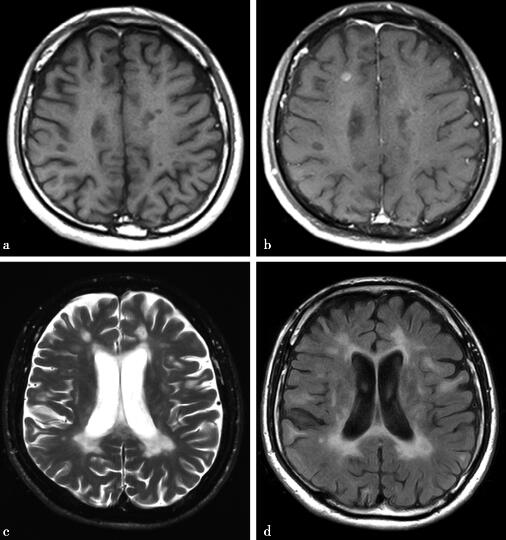

病例1-4-6:MRI T1WI、T1WI增强、T2WI、FLAIR序列。

图1a,轴位T1WI见双侧侧脑室旁及胼胝体层面白质区数个类圆形稍长T1信号影。1-4-6b,轴位T1WI增强,见右侧额叶皮层下病灶结节样强化。图1c~d,轴位T2WI和FLAIR序列。图1a,见病灶呈稍长T2信号影

慢性MS患者脑萎缩常见,发作期MS斑块可见强化,CT平扫斑块通常呈低密度。MRI扫描斑块通常为长T1长T2信号,T2-FLAIR序列可见脑室周围垂直向多发卵圆形高信号,形成Dawson指表现,对于幕上皮质旁及脑室旁病灶T2-FLAIR序列较普通T2WI敏感,而对于幕下病灶则T2WI较敏感。增强扫描活动期病灶通常呈环形强化,其中“半环”状强化较为特征性,同时活动期病灶DWI可见弥散受限。具体请参阅2010年版McDonald MS MRI诊断要点。